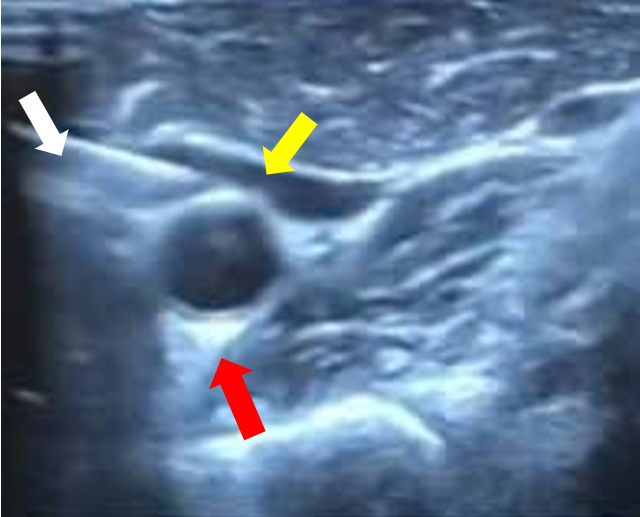

Chọc hút hạch nghi ngờ sát động mạch cảnh dưới hướng dẫn siêu âm (mũi tên trắng: kim sinh thiết, mũi tên vàng: hạch nghi ngờ, mũi tên đỏ: Động mạch cảnh)

(mũi tên trắng: kim sinh thiết, mũi tên vàng: hạch nghi ngờ, mũi tên đỏ: Động mạch cảnh)